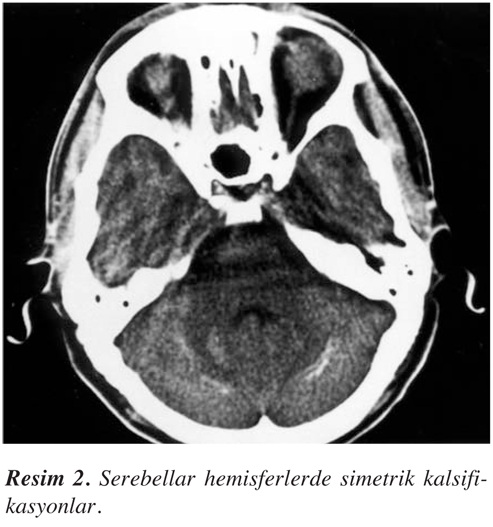

Nörolojik muayenede bilinç açık ve koopere idi. Yapılan kısa mental durum testinde (mini mental state- MMST), mental işlevlerde orta derecede bozukluk saptandı. MMST skoru 23 bulundu. Bu tabloda dikkat ve konsantrasyon bozukluğu gibi daha çok frontal işlev bozukluğu hakimdi. Derin tendon refleksleri hipoaktifti. Her iki gözde katarakt mevcuttu. Serebellar testlerde bilateral hafif dismetri ve disdiadokokinezi saptandı. Tonus üst ekstremitelerde hafif artmıştı. Duyu ve motor muayene normaldi. Patolojik refleks saptanmadı. EEG’de hafif ve yaygın organizasyon bozukluğu zemininde bilateral temporal ve frontal bölgelerde intermittan ritmik delta yavaşlamaları gözlendi. BT incelemesinde bazal ganglionlarda belirgin olmak üzere her iki serebral hemisferde subkortikal bölgelerde ve serebellar hemisferlerde yaygın, yoğun ve simetrik kalsifikasyonlar saptandı (Resim 1 ve Resim 2).

İntrakranial kalsifikasyonlar, hipoparatiroidinin oldukça sık görülen bir özelliğidir ve başlıca bazal ganglionlarda görülür (1,3,6-8). Ayrıca serebellar hemisferlerde, dentat nukleusta, nukleus ruberde, hipokampusta ve serebral kortekste de ortaya çıkabilir (1,2,4-7). Topografik olarak başlıca lokalize, multipl yama tarzında ve bilateral simetrik kalsifikasyonlar olarak sınıflandırılırlar. Bazal ganglion kalsifikasyonları en sık globus pallidusta görülür. Yaşlılarda fizyolojik olarak punktat ve hafif düzeyde bulunabilir. Putamen lokalizasyonlu olanlarda hipoparatiroidi veya psödohipoparatiroidi düşünülmelidir (1).

Semptomların genellikle lokalizasyonla ilişkili olmadığından sözedilmekle birlikte parkinsonizm, koreatetoz ve tremor gibi ekstrapiramidal bulgulara sık rastlanır (6,7,11,12). BT’deki kalsifikasyon lokalizasyonları her zaman klinik bulgularla korelasyon göstermese de (12), manyetik rezonans ile yapılan bir çalışmada, nörolojik manifestasyonların kalsifikasyonların lokalizasyonu ile sıkı ilişkisi vurgulanmaktadır (11). Hipoparatirodizmde serebellar hemisferler ve subkortikal bölgelerde de kalsifikasyon bulunabilir. Bizim olgumuzda da bilateral ve simetrik olmak üzere bu bölgelerde kalsifikasyon vardı. Oysa Fahr hastalığında daha çok bazal ganglion tutulumu belirgindir ve subkortikal beyaz cevher korunmuştur. Ayrıca Fahr hastalığında otozomal dominant veya resessif geçiş sözkonusu olup paratiroid metabolizması bozukluğu olmadan kalsiyum ve demir depositleri birikmektedir (1,8,11,13). Olgumuzun aile öyküsünde böyle bir hastalığa rastlanmamıştır. Kafa içi basınç artışı ve papil ödemi, hipoparatiroidili bazı olgularda rastlanabilir. Psödotümör serebri, serum kalsiyumunun düzeltilmesi ile normale döner (3,8).